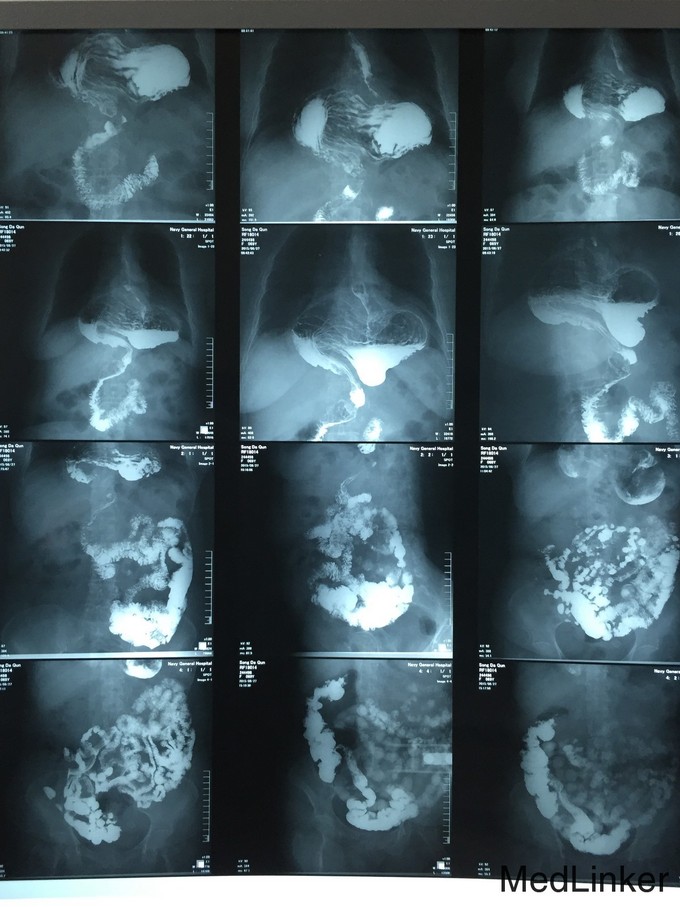

心脏彩超提示:左室收缩功能62%,左房稍大,主动脉瓣轻度关闭不全,左室舒张功能减低(2015-04-02 海军总医院); 胃镜:反流性食管炎、食管旁疝、慢性非萎缩性胃炎(2015-08-24 海军总医院); 全消化道造影:食管裂孔疝,胃大部疝入胸腔(2015-08-27 海军总医院); 冠脉CTA提示:左冠状动脉主干及前降支近段多发钙化斑块影,管腔多发轻中度狭窄,对角支中段钙化斑块形成,管腔中度狭窄,右侧冠脉中远段钙化斑影,管腔局部轻度变窄(2015-09-01 海军总医院); 胸部CT:食管裂孔疝形成伴部分肺组织膨胀受限伴肺内少许慢性炎性变(2015-09-02 海军总医院)。